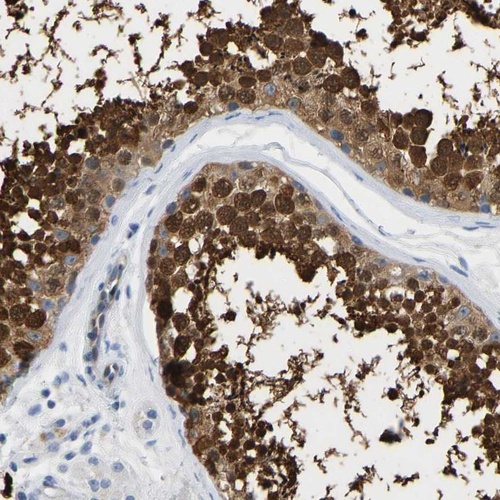

Immunohistochemical staining of human testis shows strong cytoplasmic and nuclear positivity in cells in seminiferus ducts.